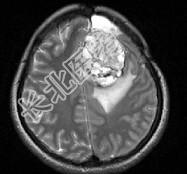

- 单项选择题女,39岁, 三年前因左额部胶质瘤手术治疗,最近出现头痛, 并抽搐大发作1次,请根据所提供图像, 选择最可能的诊断是 ( )

A、(左额叶)放射性脑炎

B、(左额叶)脑脓肿

C、(左额叶)脑出血

D、(左额叶)脑转移瘤

E、(左额叶)星形细胞瘤Ⅱ~Ⅲ级